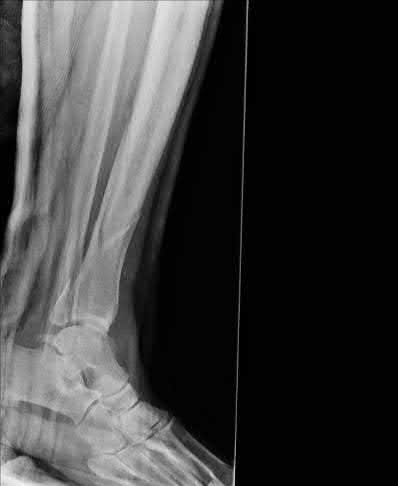

A 25-year-old female is involved in a motor vehicle collision. She presents with the isolated injury seen in Figures A through D. Her leg is swollen but her skin is intact. She has no clinical signs of compartment syndrome. Which of the following treatment options will allow for maintenance of fracture alignment and minimize the risk of soft tissue complications?

The patient presents with a closed distal third metaphyseal-diaphyseal distal tibia fracture with simple intra-articular extension. Immediate intramedullary nailing along with percutaneous fixation of the articular component provides appropriate restoration of length, rotation and alignment and minimizes the risk of wound complication.

Displaced distal third tibia fractures may be associated with simple intraarticular extension. Operative treatment of intra-articular distal tibia fractures has historically been performed with open reduction and internal fixation. Early open reduction and plate fixation of pilon fractures has been associated with high rates of infection and wound complication. In select patterns with simple articular extension, percutaneous screw fixation and medullary nailing may provide appropriate reduction with minimal soft-tissue risk.

Marcus et al. evaluated the outcomes of immediate intramedullary nailing and percutaneous fixation of simple intra-articular distal tibia fractures (AO/OTA 43 C1 and C2). The authors found excellent rates of union and alignment, however caution against broad application of this technique until more rigorous randomized studies can be performed.

Sirkin et al. retrospectively evaluated the results of a staged approach to management of intra-articular distal tibia fractures with temporary bridging external fixation followed by open reduction and internal fixation (ORIF). The authors found decreased rates of wound complication and infection compared with prior studies.

Figures A and B demonstrate a distal third tibial shaft fracture with simple intra-articular extension. The axial and coronal CT cuts in Figures C and D further clarify the articular injury. Illustrations A and B demonstrate a comminuted distal third tibial fracture with simple intra-articular extension. Illustrations C and D are fluoroscopic images of the same injury after intramedullary nailing and percutaneous fixation of the articular component.